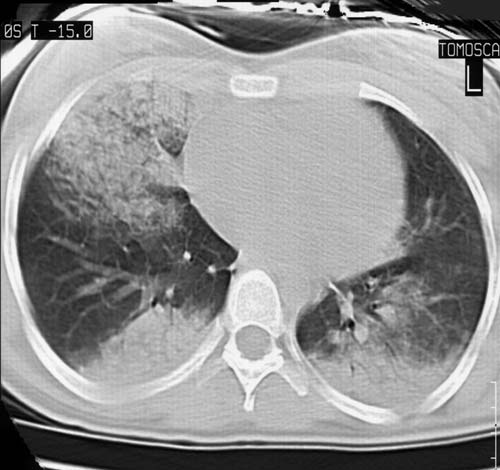

Syndrome alvéolaire

niveau de la coupe

TDM